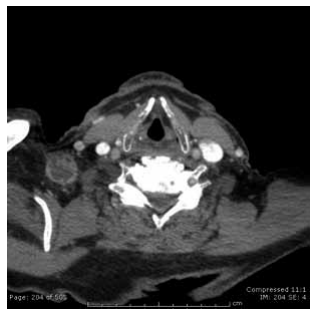

Homem de 23 anos com linfonodomegalia de 2 cm, conforme demonstrada na imagem a seguir, com suspeita de doença linfoproliferativa.

Enunciado 4425211-1

(Arquivo pessoal; imagem usada com autorização)

Assinale a alternativa que apresenta os cuidados cirúrgicos necessários durante a biópsia excisional.